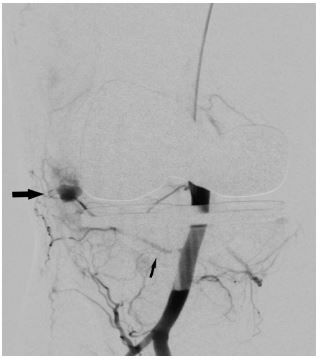

In view of continued knee joint swelling, the patient underwent right lower limb angiography the following week through the right femoral artery approach which identified a Pseudoaneurysm arising from the inferior medial genicular artery. This was embolized using 250 microns’ particles- embospheres and 2mm push able coils. Selective angiogram performed from superior medial and lateral genicular artery showed abnormal blush and pruning was done using 250-micron embospheres (Figures 3,4 & 5). An Ice pack was placed over the knee while instilling embolic agent particles to cause vasoconstriction of the skin arterial supply to avoid ischemia.

Figure 5: Post embolization using particles- embospheres and coils (solid arrow) angiography shows non opacification of the pseudoaneurysm.